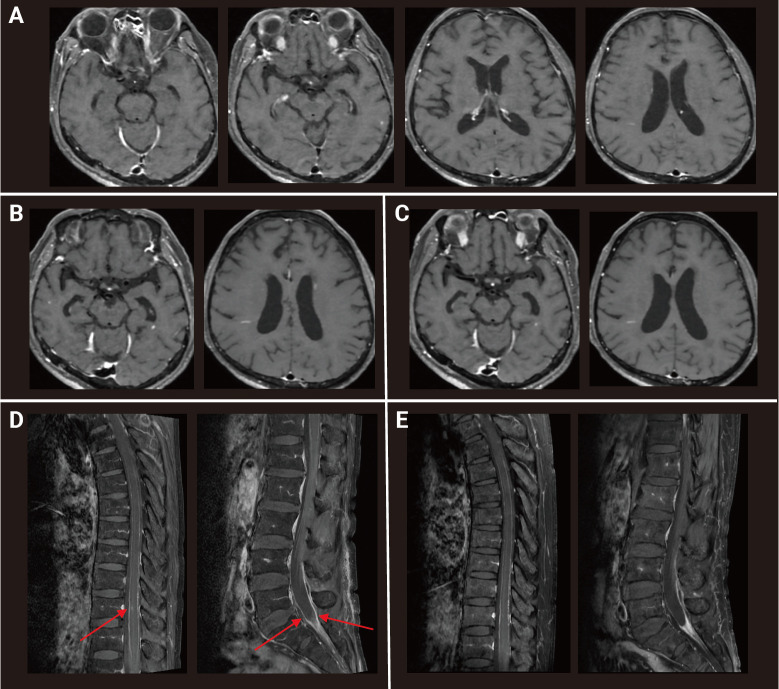

Eosinophilic meningoencephalitis is a rare inflammatory condition of the central nervous system. As a limited number of cases has been reported, debate remains on the optimal treatment. We present a case of idiopathic eosinophilic meningoencephalitis successfully treated with glucocorticoids and intravenous immunoglobulin (IVIG). After extensive evaluation to rule out other possible causes, the patient was treated with intravenous (IV) dexamethasone and showed significant improvement within a few days. However, neurologic impairment persisted, and follow-up lumbar puncture results showed only a mild decrease in pleocytosis. Even after an additional 5 days of IV methylprednisolone, cerebrospinal fluid (CSF) pleocytosis persisted, and brain magnetic resonance imaging (MRI) showed an increase in enhanced lesions, implying persistent neuroinflammation. The patient was maintained on high-dose oral prednisolone for 2 months, and additional immune-modulatory effects were treated with IVIG. Follow-up MRI at 2 months showed a significant decrease in the extent of multiple enhanced lesions and a normalized CSF profile. The patient was maintained on regular maintenance doses of IVIG for an additional 6 months without any neurologic signs or symptoms. Inflammation is the key pathophysiology underlying neurological damage in eosinophilic meningoencephalitis. A literature review revealed that corticosteroid treatment is the only anti-inflammatory treatment used in cases of idiopathic meningoencephalitis, resulting in sufficient response in most patients but only partial response or death in a few cases. This is the first case report of IVIG use in idiopathic eosinophilic meningoencephalitis, suggesting the possibility of a new treatment modality for refractory cases.